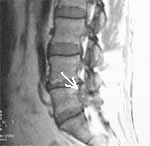

Остеофиты имеют различную интенсивность МРТ-сигнала, в зависимости от содержания костного мозга. Они могут быть бедны сигналом на всех изображениях или на T1w давать высокий сигнал, а на T2w - сигнал средней интенсивности. В первом случае дифдиагностика остеофитов с тканью диска, имеющей низкий сигнал, затруднена. В 2-х случаях при обычных исследованиях такие остеофиты были приняты за грыжи дисков и больные с узким спинно- мозговым каналом были оперированы. Применение Т2 GRE последовательности могло помочь в дифференциации остеофита и ткани диска. На данных изображениях компактные остеофиты дают более низкий сигнал, чем ткань диска. GRE-последовательности предпочтительнее для выявления костного стеноза, однако менее информативны в трактовке интрамедуллярного процесса (Рис. 2).

Рис. 2. Обызвествленная пролабированная часть диска L5-S1 в правом латеральном кармане. (а) Имеет пониженную интенсивность при GRE  последовательности (стрелка).

Рис. 2. Обызвествленная пролабированная часть диска L5-S1 в правом латеральном кармане. (б) Обызвествление хорошо видно на КТ.

Следует отметить, что КТ четко выявляет признаки деформирующего остеоартроза суставов, остеофиты, обызвествленную часть диска, обызвествление и окостенение связок.